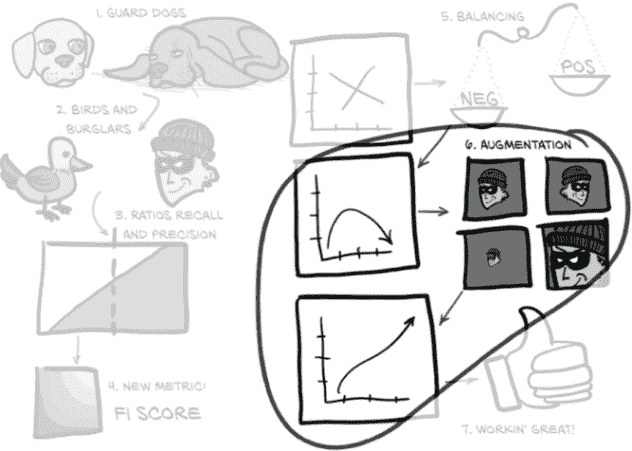

虽然有点抽象,图 12.2 向我们展示了我们将如何处理那些广泛的主题。

让我们详细地走过本章的这张有些抽象的地图。我们将处理我们面临的问题,比如过度关注单一、狭窄的指标以及由此产生的行为在一般意义上是无用的。为了使本章的一些概念更具体化,我们将首先使用一个比喻来将我们的困境更具体化:在图 12.2 中,(1)看门狗和(2)鸟和窃贼。

图 12.2 我们将使用的比喻来修改衡量我们模型的指标,使其变得出色

之后,我们将开发一个图形语言来代表上一章实施中所需的核心概念:(3)比率:召回率和精确率。一旦我们将这些概念巩固下来,我们将涉及一些使用这些概念的数学,这将包括一种更健壮的评估我们模型性能的方式,并将其压缩为一个数字:(4)新指标:F1 分数。我们将实施这些新指标的公式,并查看在训练过程中每个时期这些结果值如何变化。最后,我们将对我们的LunaDataset实现进行一些急需的更改,以改善我们的训练结果:(5)平衡和(6)增强。然后我们将看看这些实验性的更改是否对我们的性能指标产生了预期的影响。

到本章结束时,我们训练的模型将表现得更好:(7)工作得很棒!虽然它还没有准备好立即投入临床使用,但它将能够产生明显优于随机的结果。这意味着我们已经有了可行的第 4 步实现,结节候选分类;一旦完成,我们可以开始考虑如何将第 2 步(分割)和第 3 步(分组)纳入项目中。